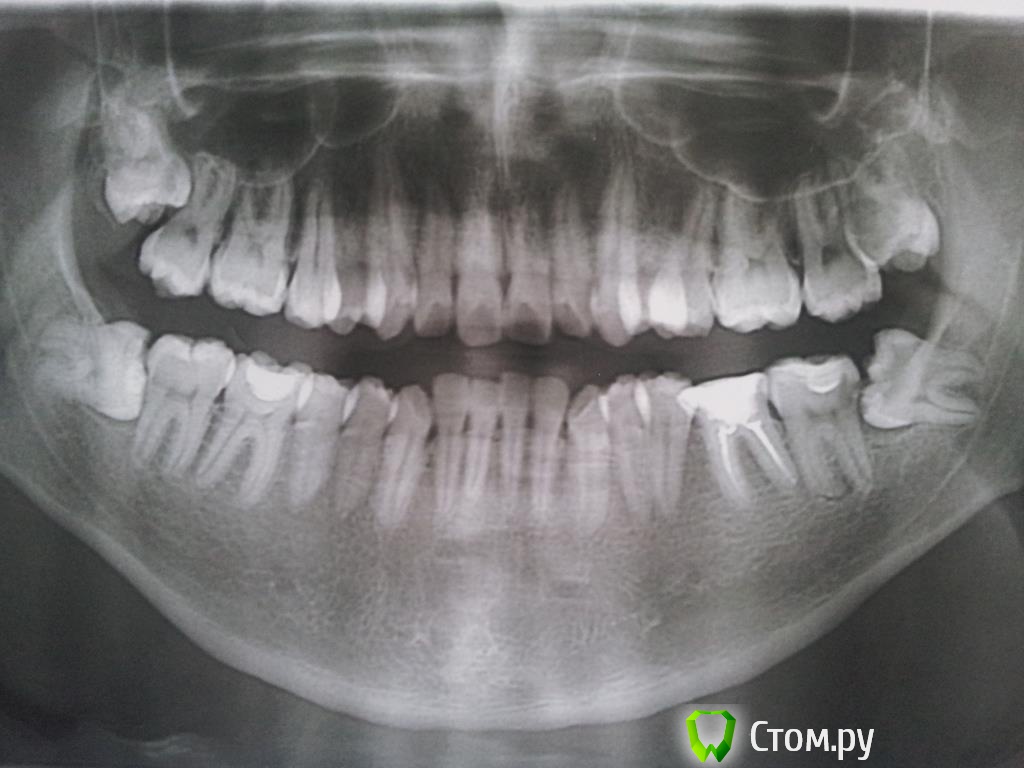

developer13 Опубликовано 22 января, 2014 Поделиться Опубликовано 22 января, 2014 (изменено) Здравствуйте, мне 25 лет, догадываюсь, что все мои восьмерки подлежат удалению. Год назад удалил 38 (на снимке она соответственно справа снизу, я правильно понимаю?).Удаление длилось часа 2, кровотечение было почти сутки, жутко болело горло что не мог ничего глотать и потом еще дня 3-4 мучали боли. Врач при удалении прописывал 7-дневный курс цефазолина в уколах 3 раза в день.В целом удаление и заживление прошло успешно, к врачу никаких претензий нет, но всё это несколько травмировало мою психику и отношение к стоматологии)) Ощущения во время и после удаления показались мне жутко неприятными (одну ночь вообще не смог спать из-за болей) что после заживления надолго отложил дальнейшие походы к стоматологу из-за страха болей и кровотечений. Но спустя год снова занялся лечением зубов, вылечил пульпит 37, кариесы 26, 27 и еще какие-то мелкие.Ну и сейчас вопрос подошел к тому, чтобы удалить 48, но хочется удалить наименее травматично и чтобы зажило как можно быстрее. Ну и просто мне страшно и немного нервничаю)) Тот же врач, что удалял 38, говорит что удаление 48 будет еще более травматичное и сложное, чем было 38. Сказал что кроме того 48-ой зуб лежит на нерве. Операцию обещает как минимум 2-3 часа, а также говорит что как минимум неделю точно будет очень тяжело и невозможно заниматься какими-либо делами (а на данный этапе в моей работе крайне нежелательно выпадение недели рабочего времени), ну и неделю нужно будет ставить уколы соответственно. Еще сказал что 47 вероятней всего в будущем придется депульпировать из-за оголения корней. В общем и целом интересует ваше мнение по этому вопросу. Как удалить 48 наименее травматично? Удаление действительно очень сложное? Описанный врачом процесс заживления неизбежен или же есть специалисты, которые сделают это аккуратнее и быстрее? Заранее благодарен. P.S. ОПТГ сделана год назад до удаления 38, врач сказал что новую пока делать нет смысла. Изменено 22 января, 2014 пользователем developer13 Ссылка на комментарий